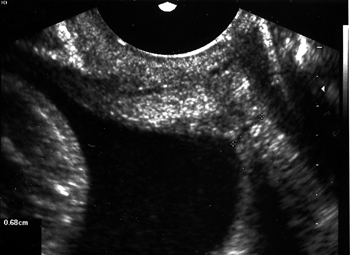

Εικόνα 1. Φυσιολογικό

μήκος τραχήλου (διακολπικό υπερηχογράφημα).